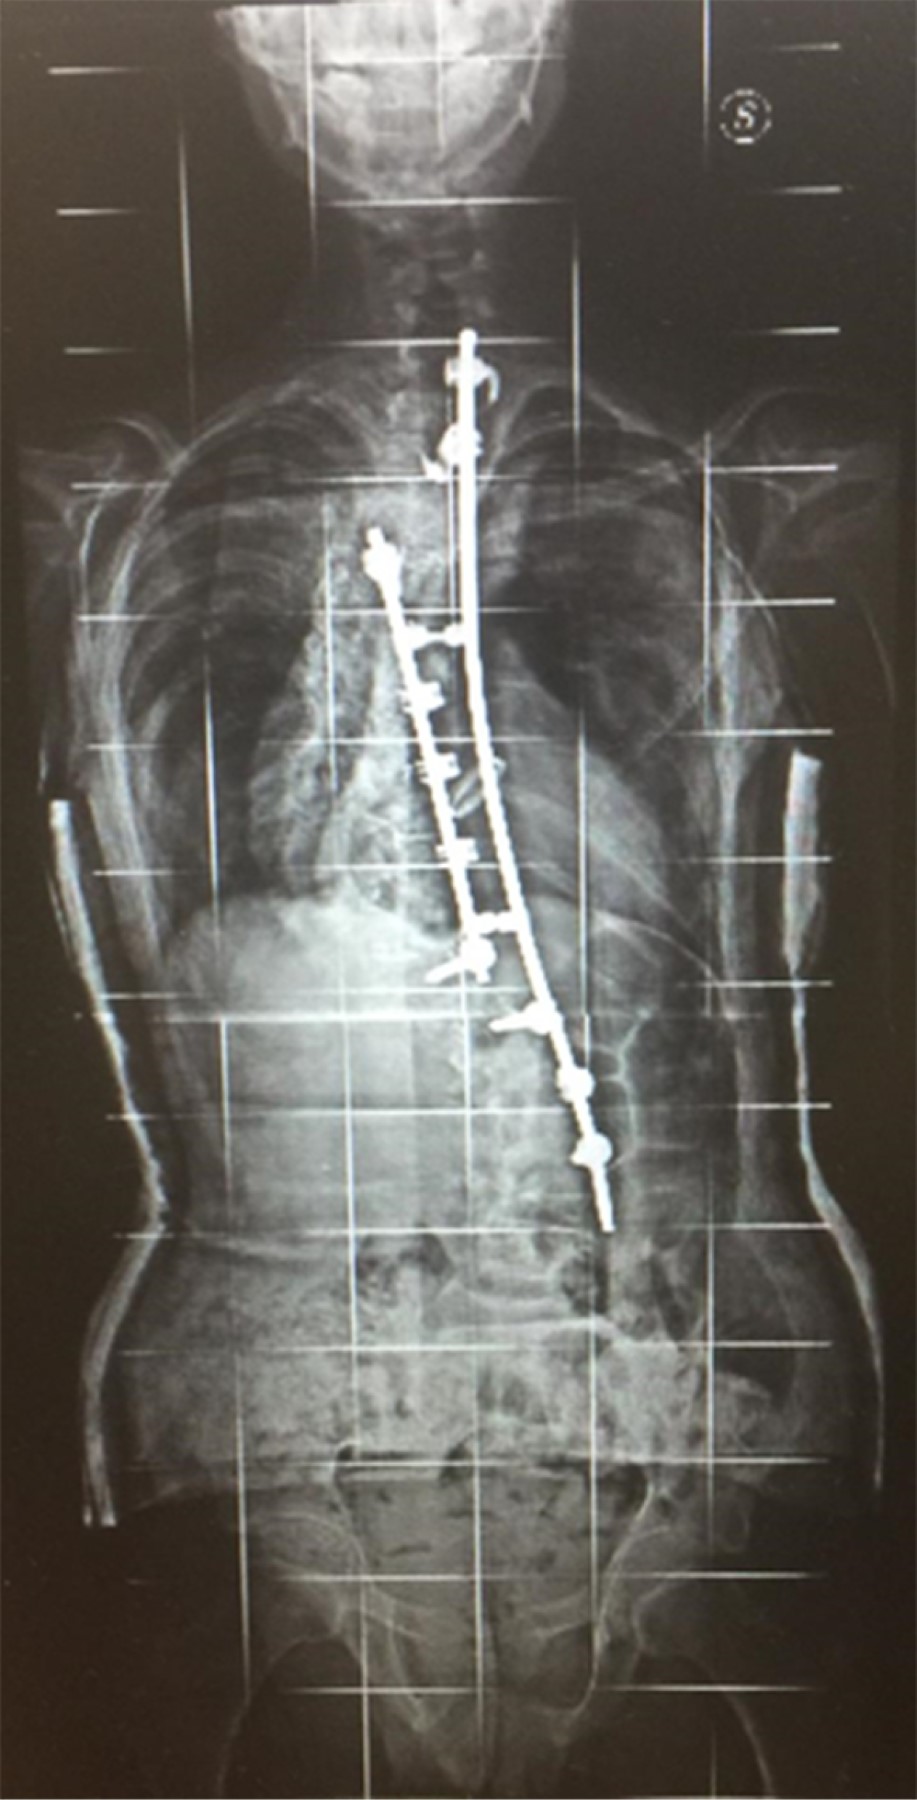

Parto a término controlado sin complicaciones prenatales ni perinatales. El peso al nacer fue de 4,400 g (DE 3.1) y la talla de 52 cm (DE 1.5). Se evidenció adecuado desarrollo sicomotor. Se mantiene en seguimiento por talla alta, hiperlaxitud ligamentaria (puntaje en la escala de Beighton 7/9), escoliosis de grado severo y progresivo con estudio de radiografía simple que describe curva escoliótica dextroconvexa a nivel dorsal, con ángulo de 102o (vértebra neutra D5-L1) y curva de compensación convexa izquierda a nivel lumbar de alrededor de 80o (vértebra neutra L1-L5), en posición lateral invariada la cifosis dorso-lumbar respecto a estudios previos. Posterior a intervención quirúrgica por rotoescoliosis dorso-lumbar dextroconvexa con presencia de dos barras metálicas estabilizadas con tornillos y ganchos. La curva escoliótica presenta un ángulo de alrededor de 53o (D4-L2) (Figura 1).

Figura 1